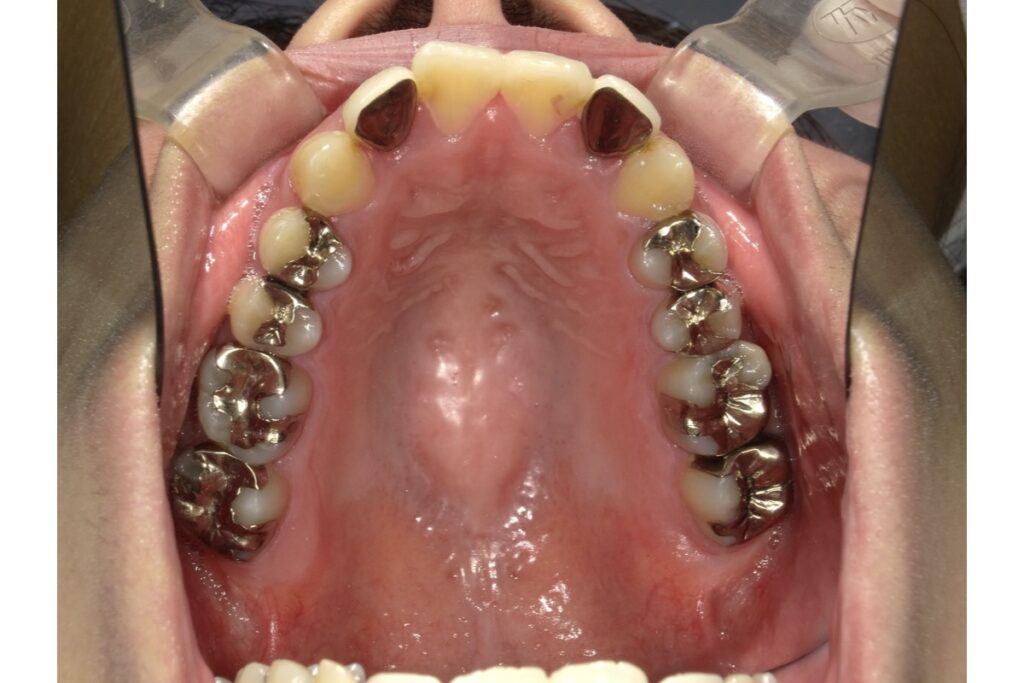

被せ物があっても矯正治療はできる?

結論から言うと、被せ物(クラウン・差し歯・インレーなど)があっても矯正治療は可能です。

ただし、「どの歯に、どんな種類の被せ物があるか」によって、治療方法に調整が必要になることがあります。

👇 被せ物の種類と矯正への影響

【1】クラウン(被せ物)

金属やセラミックなどで歯を全体的に覆っているタイプの被せ物。

→ 基本的に、ブラケット装置を装着することは可能です。

ただし、接着が弱くなることがあるため、特別な接着剤を使ったり、別の方法(バンド使用など)で固定することがあります。

【2】インレー(詰め物)

歯の一部に詰めるタイプ(銀歯・ハイブリッドなど)

→ 基本的に矯正にはほとんど影響なしです。